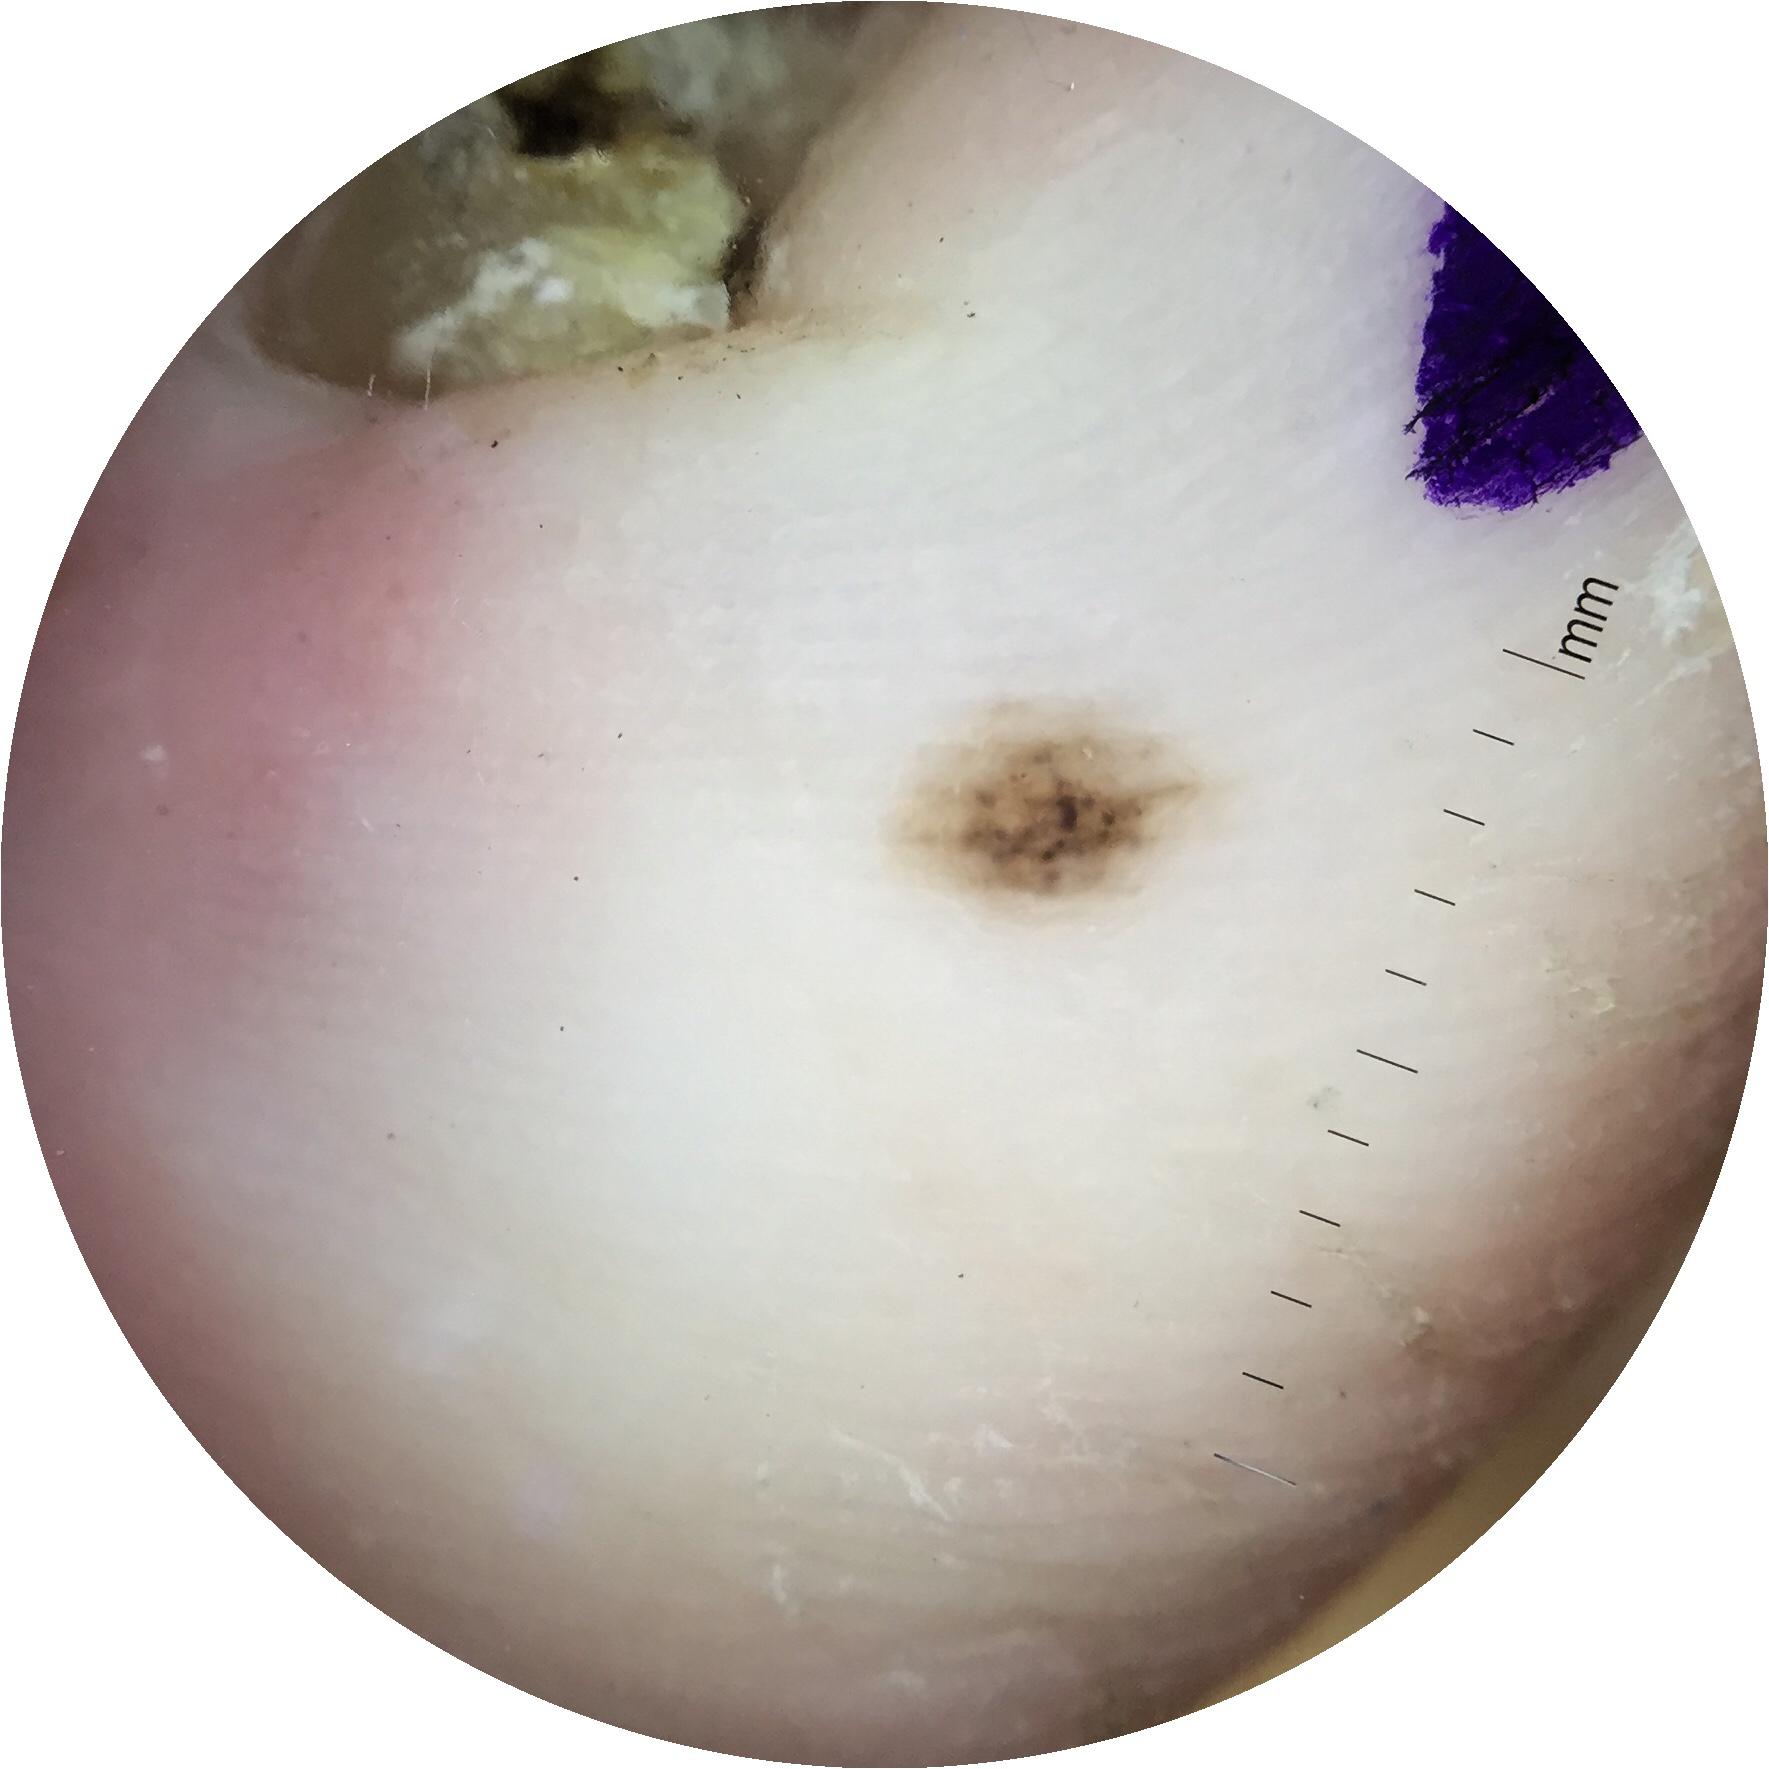

{

"age_approx": 45,

"anatom_site_general": "lower extremity",

"anatom_site_special": "acral NOS",

"concomitant_biopsy": true,

"diagnosis_1": "Benign",

"diagnosis_2": "Benign melanocytic proliferations",

"diagnosis_3": "Nevus",

"diagnosis_4": "Nevus, NOS, Compound",

"diagnosis_confirm_type": "histopathology",

"image_type": "dermoscopic",

"lesion_id": "IL_2578843",

"melanocytic": true,

"patient_id": "IP_8137203",

"sex": "female"

}